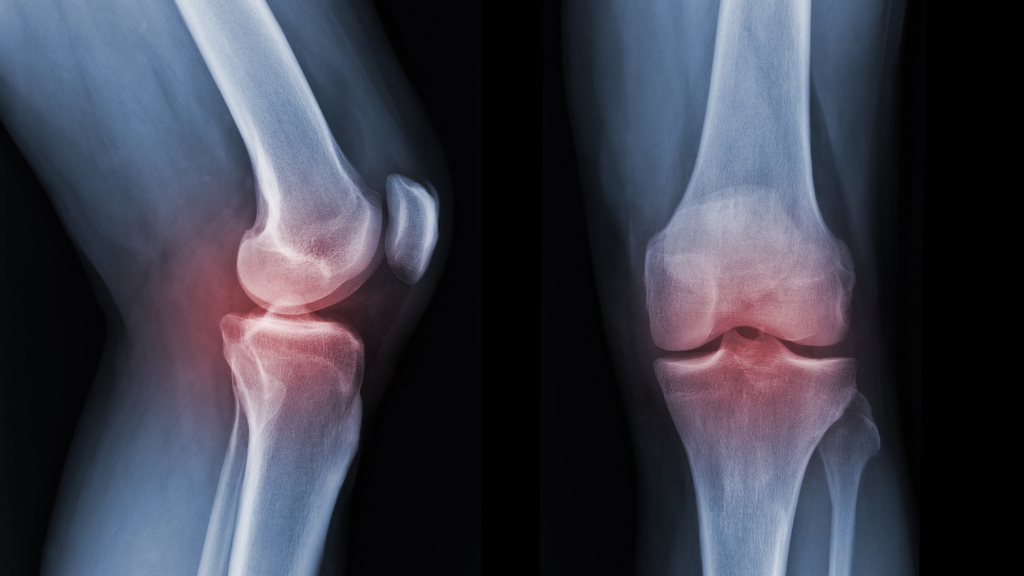

Chẩn đoán nứt xương bánh chè bằng cách nào?

Chẩn đoán nứt xương bánh chè cần được thực hiện bởi bác sĩ chuyên khoa chấn thương chỉnh hình nhằm phân biệt với các tổn thương phần mềm quanh khớp gối. Do triệu chứng lâm sàng có thể không điển hình, việc kết hợp thăm khám và phương tiện chẩn đoán hình ảnh là rất quan trọng.

- Khám lâm sàng chuyên khoa: Bác sĩ sẽ khai thác tiền sử chấn thương, cơ chế gây tổn thương và đánh giá các triệu chứng như đau khu trú vùng xương bánh chè, sưng nề, bầm tím và mức độ hạn chế vận động khớp gối. Khám lâm sàng giúp định hướng ban đầu nhưng không đủ để khẳng định chẩn đoán.

- Chụp X-quang khớp gối: X-quang là phương tiện chẩn đoán hình ảnh cơ bản và thường được chỉ định đầu tiên. Phim X-quang có thể giúp phát hiện vết nứt xương bánh chè, đánh giá vị trí và mức độ tổn thương. Tuy nhiên, một số vết nứt nhỏ hoặc không di lệch có thể khó nhận thấy trên X-quang thường quy.

- Chụp CT khi cần thiết: Trong trường hợp X-quang không rõ ràng hoặc nghi ngờ tổn thương phức tạp, CT scan giúp quan sát chi tiết cấu trúc xương, xác định chính xác đường nứt và mức độ lan rộng của tổn thương.

- Chụp MRI trong các trường hợp đặc biệt: MRI không phải phương tiện chẩn đoán đầu tay cho nứt xương bánh chè, nhưng có giá trị khi cần đánh giá thêm các tổn thương đi kèm như sụn khớp, dây chằng, gân cơ hoặc tràn dịch khớp gối.